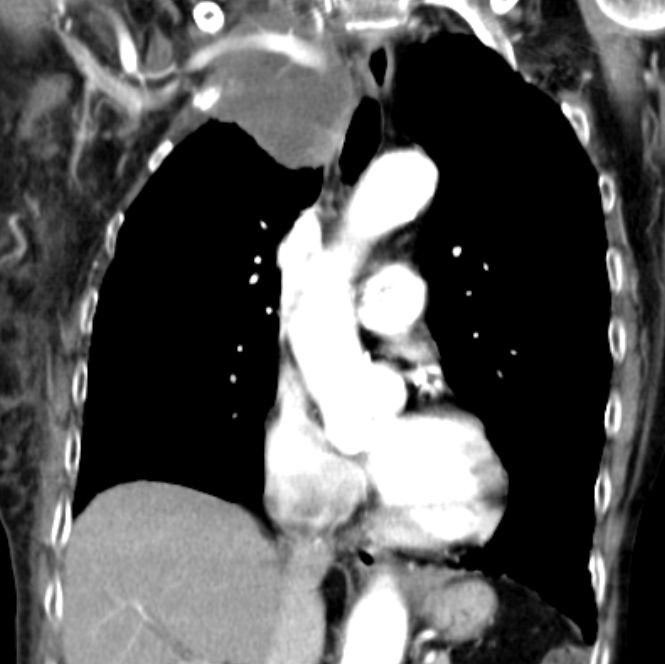

| Embolie | 55-jähriger Mann mit SCC rechts zentral mit

Verschluss der Mittellappens und Stenose des Zwischenbronchus T4 N2b Mo. Vom

Tumor eingeschlossen eine Pulmonalarterie mit einer kreisrunden Aussparung

durch einen Embolus.![]()  | ||